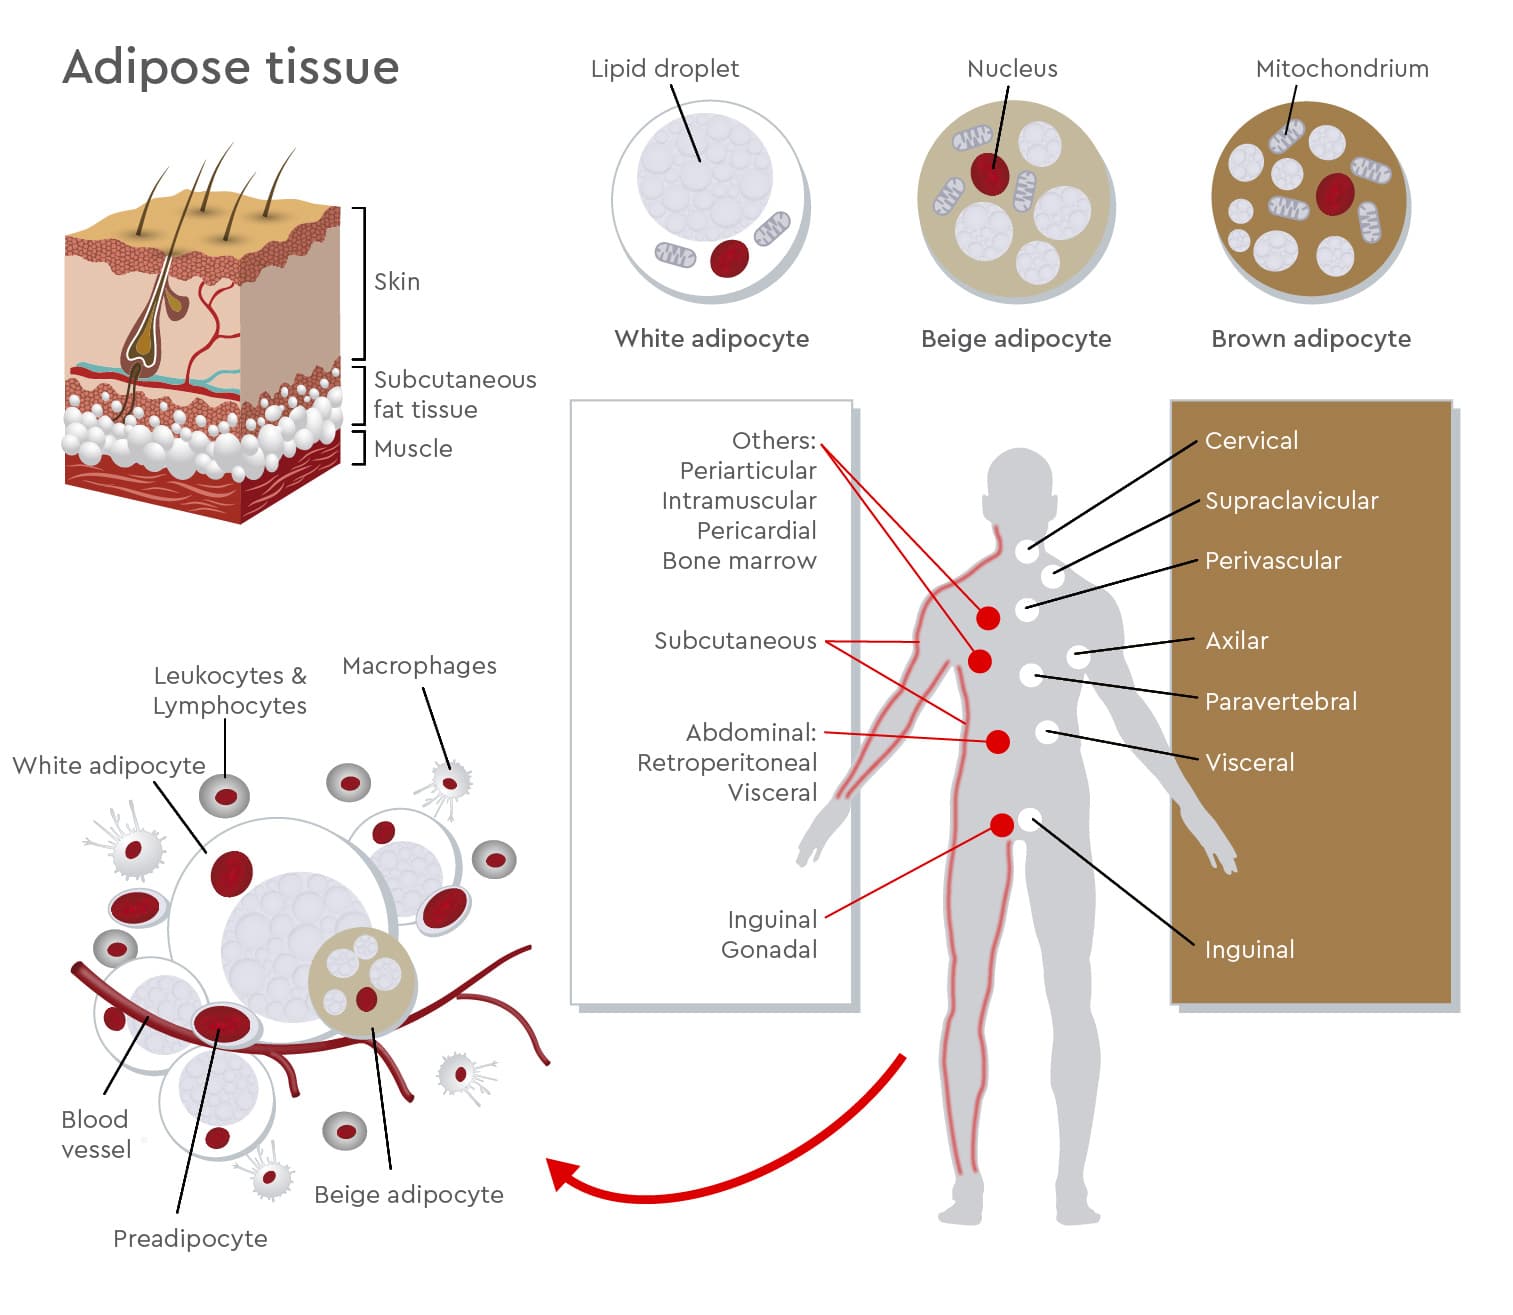

Figure 1: Adipose tissue structure and adipocyte diversity.

Adipose tissue contains mature adipocytes together with preadipocytes, immune cells, macrophages, blood vessels, and other stromal cell populations. White, beige, and brown adipocytes differ in lipid droplet structure, mitochondrial content, and metabolic function. These adipocyte types are found across different anatomical depots and contribute to energy storage, endocrine signalling, thermogenesis, and metabolic regulation.

Humans have different adipocyte types with distinct but partly overlapping functions. White adipocytes primarily support energy storage and endocrine signalling, brown adipocytes are specialized for heat production, and beige or brite adipocytes can acquire thermogenic, brown-like features in response to specific stimuli.

White adipocytes are large cells that usually contain one dominant lipid droplet and fewer mitochondria than thermogenic adipocytes. They store excess energy as triglycerides and release fatty acids when energy is needed. White adipose tissue also acts as an endocrine organ, secreting adipokines, cytokines, and other signalling molecules involved in appetite regulation, inflammation, insulin sensitivity, cardiovascular activity, and tissue remodelling.1

Brown adipocytes are smaller, mitochondria-rich cells with several lipid droplets. They generate heat through thermogenesis and contribute to energy expenditure. Beyond heat production, brown adipocytes also secrete signalling molecules that may influence local and systemic metabolism.2

Beige, or brite, adipocytes are inducible thermogenic adipocytes found within white adipose tissue depots. At baseline, they can resemble white adipocytes, but after stimulation, such as cold exposure or adrenergic signalling, they may acquire brown-like features, including higher mitochondrial activity and thermogenic capacity.3 This reflects the plasticity of adipose tissue rather than a fixed, one-directional cell identity.